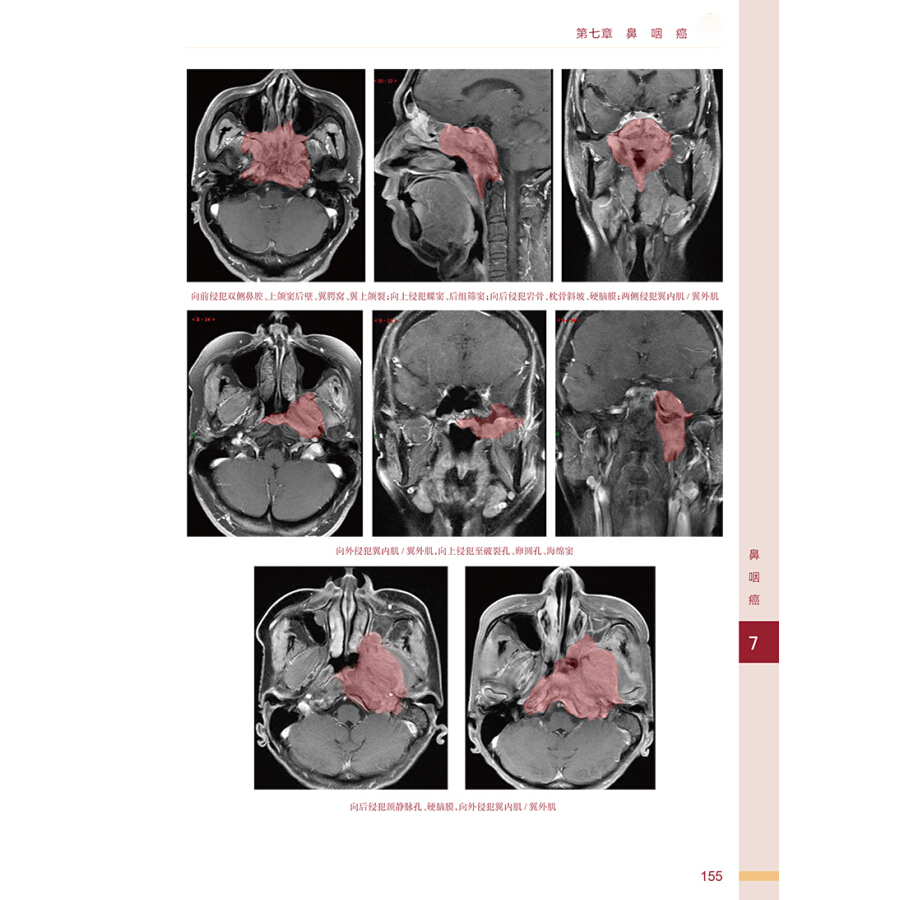

第七章 鼻咽癌 / 148

第一节 应用解剖 / 149